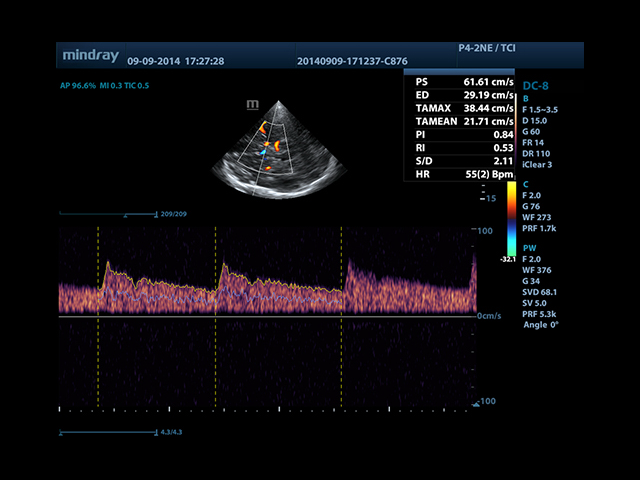

• Автоматическая трассировка допплеровского спектра с расчетом параметров и индексов

• Smart Doppler™ - автоматическая подстройка расположения рамки цветового допплера и контрольного объема импульсно-волнового допплера

• Секторный датчик Mindray P4-2E